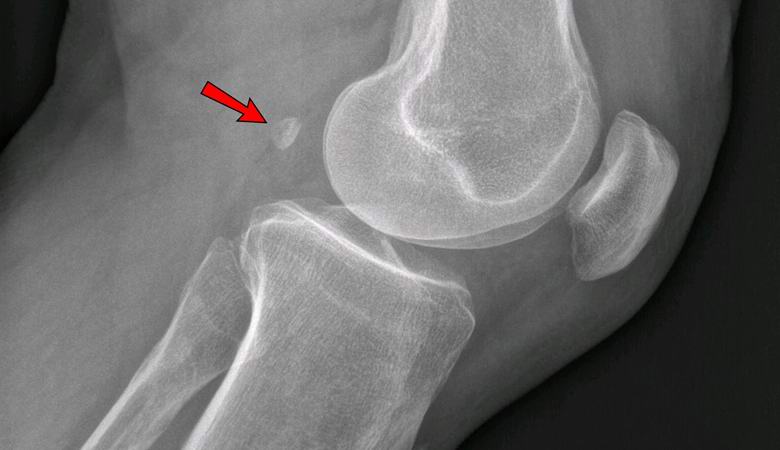

Jos vuonna 1918 vain 11 prosentilla maalaisista oli fabella ainakin yhdessä jalka, sitä esiintyy tänään 39 prosentilla ihmisistä. Tämä seesaminmuotoinen luu kasvaa jänteiden paksuudessa polven takana ja anatomisesti muistuttaa mikroskooppista patellaa.

On oletettu, että fabella meni henkilölle alkaen apinoilla, joissa hän lisäsi mekaanista tehokkuutta polvinivelet. Ihminen, he sanovat, kehittyi ja alkoi menettää annettu luu. Tästä huolimatta viime vuosikymmeninä enemmän ihmiset alkoivat kärsiä ylipainosta rasvaisen ruokavalion vuoksi ja väärä elämäntapa. Paine polvinivelillemme lisääntynyt, ja juuri sen väitetään johtavan “kadonneen” muodostumiseen sesamoid luu.

Nykyään jokainen biologian oppikirja osoittaa, että ihmisen luuranko koostuu 206 luusta. Ehkä kuitenkin tulevaisuudessa tällaista tietoa tunnustetaan vanhentuneiksi, ja siellä he puhuvat 206-208 luusta, koska monilla ihmisillä on jo yksi tai molemmat tarinat. tämä luu, jota monet lääkärit katsovat, voidaan kutsua lisäykseksi luuranko “, koska se ei ole vain hyödytön, vaan voi myös palvella aiheuttaa terveysongelmia. Kosketuksessa polvien rustoihin, se johtaa vakavaan nivelrikkoon.